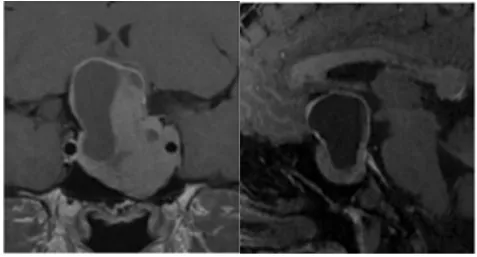

手術(shù)過程:由于視神經(jīng)腦池段和視神經(jīng)管段間明顯粘粘扭結(jié),所以先行經(jīng)鼻內(nèi)鏡視交叉分離和固定保護(圖3)。視神經(jīng)管近端磨除骨質(zhì),然后切除殘余腫瘤。使用人工硬腦膜關(guān)顱,水密縫合,防治腦脊液漏。通過橫膈膜觀察視蛛網(wǎng)膜池的視神經(jīng),并使用腹部脂肪向鞍內(nèi)填充,使用鼻中隔骨和鈦網(wǎng)重建鞍底。

較大垂體瘤耐藥又術(shù)后復(fù)發(fā)圖片

圖3:(e,f,g,h)顯示前交通動脈復(fù)合體的鞍內(nèi)疝(e),右側(cè)視神經(jīng)管鉆孔骨質(zhì)磨除(f),硬膜外剝離鞍內(nèi)腫瘤(g),然后硬膜內(nèi)切除腫瘤(h)。

術(shù)后一年,MRI顯示腫瘤全切、脂肪填充空蝶鞍(圖4)。術(shù)后左側(cè)視野好轉(zhuǎn),視力穩(wěn)定在0.3,右側(cè)視力從0.03好轉(zhuǎn)到1.0、如正常視力。

較大垂體瘤耐藥又術(shù)后復(fù)發(fā)——術(shù)后MRI圖片

圖4:術(shù)后一年MRI